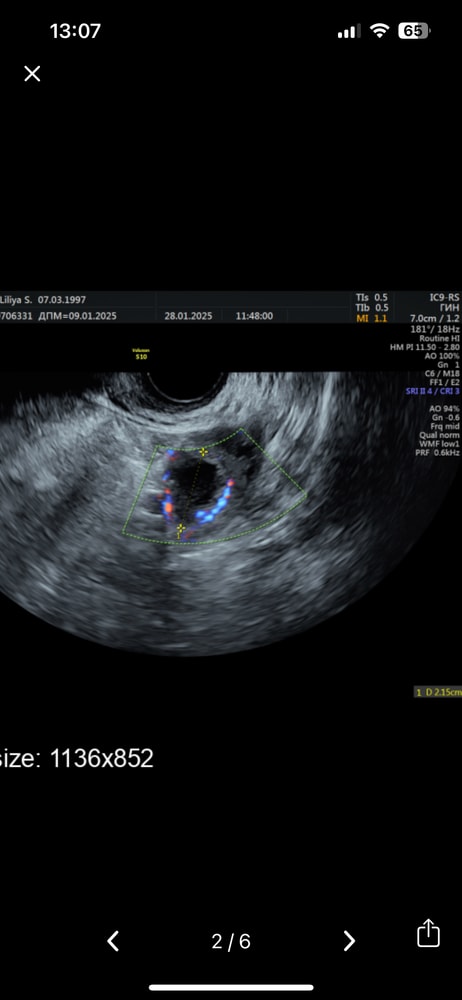

Мне кажется на фоте это Жт?